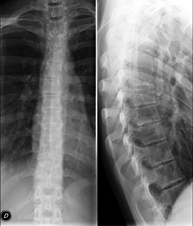

- Lumbar spine X-ray

This technique uses X-ray rendered imaging to examine the lumbar spine. Indicated for: sciatica, trauma, lower back pain.

- Spinal teleradiology

This technique uses X-ray rendered imaging to examine the entire spinal column, especially assessing the presence of scoliosis and pelvic dysmetria.